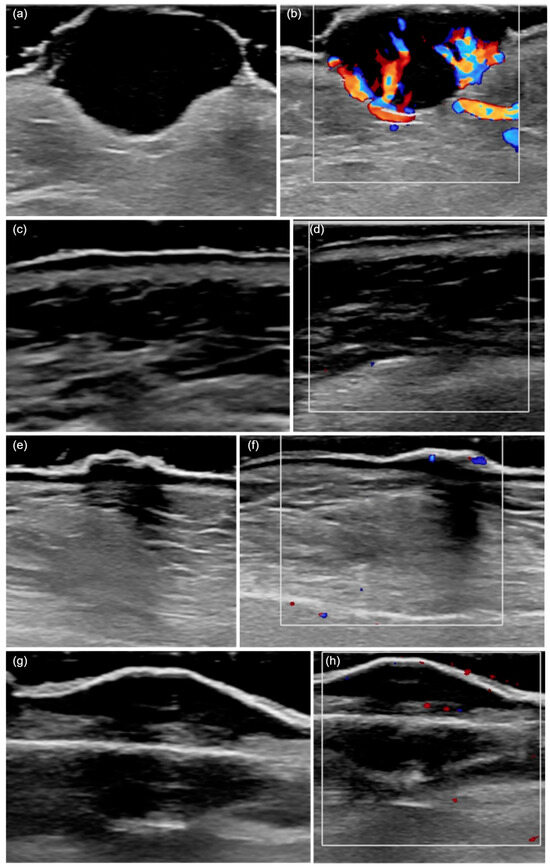

Among the most frequently encountered US criteria, we highlight imprecise boundaries (62.9%), presence of ulceration (60%), hypervascularization (71.4%), and posterior acoustic shadowing (51.4%). The main US characteristics of the tumors are shown in Table 2 and illustrated in Figure 1.

Figure 1. HFUS (20 MHz) features of cutaneous squamous cell carcinoma. (a) A hypoechoic lesion with an irregular shape and heterogeneous echogenicity, invading the deep dermis and presenting ulceration. (b) The color Doppler mode shows a marked increase in local vascularization. (c) A hypoechoic tumor confined to the epidermis, with a regular shape and homogeneous echogenicity. (d) An absence of local vascularization in color Doppler mode. (e) The presence of posterior acoustic shadowing. (f) Moderate vascularization detected in color Doppler mode. (g) A hypoechoic, regular, and poorly defined lesion invading the hypodermis, with posterior acoustic shadowing. (h) The presence of vascularization in color Doppler mode.